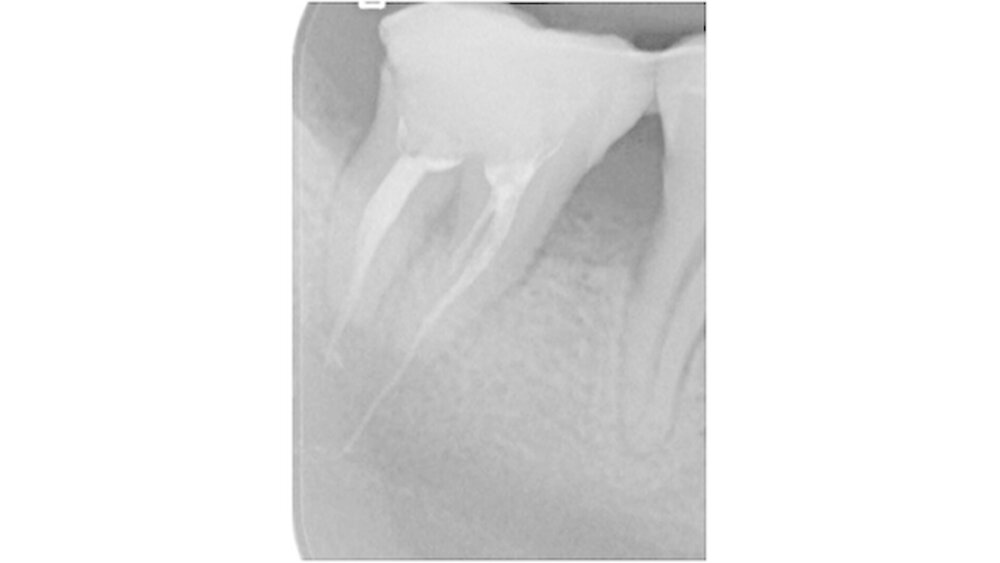

Der Zahn 47 stellte sich parodontal geschädigt und 1-gradig gelockert dar. Das Orthopantomogramm (OPTG) und der anschließend angefertigte Zahnfilm (Abbildungen 2 und 3) zeigten am Zahn 47 apikal weit überextrudiertes Wurzelfüllmaterial. Die Patientin wurde aufgrund der klinischen und der röntgenologischen Befunde sofort an die Klinik und Poliklinik für Mund-, Kiefer- und Gesichtschirurgie überwiesen.

Die dreidimensionale Darstellung des Unterkiefers rechts mittels digitaler Volumentomografie (DVT, Abbildung 4) vervollständigte den Nachweis von röntgenopakem Material im Bereich der Wurzelspitzen des Zahnes 47 mit direktem Kontakt zum Nervus alveolaris inferior. Die Rücksprache mit dem ausländischen Behandler ergab die Information, dass es sich bei dem Füllmaterial um Guttapercha zusammen mit einem paraformaldehydhaltigen Zement handelte.